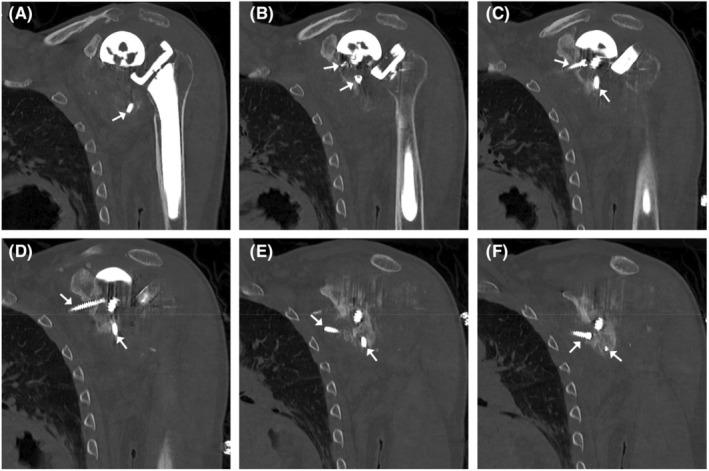

Manual wheelchair users place high stress on their shoulders. We describe a 69-year-old male who developed end-stage shoulder osteoarthritis from chronic manual wheelchair (MW) use. Three prosthetic total shoulder replacements failed, reflecting his refusal to transition to an electric wheelchair. MW use must be avoided in some of these patients.

手动轮椅使用者的肩部承受着巨大压力。我们描述了一名69岁男性,他因长期使用手动轮椅而患上了终末期肩部骨关节炎。三次人工全肩关节置换手术均告失败,这反映出他拒绝改用电动轮椅。在这类患者中,有些必须避免使用手动轮椅。